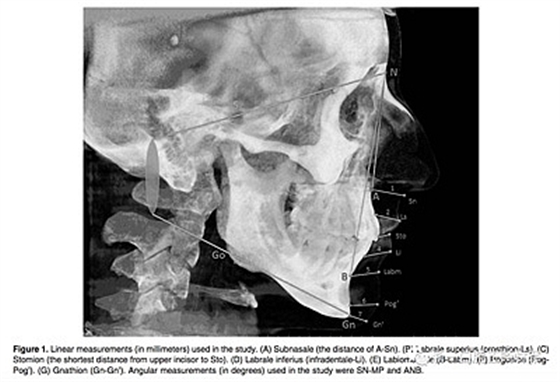

所有患者拍攝頭顱CBCT,要求以最大的牙尖交錯位, 放松嘴唇位置, 不能移動他們的頭部或舌頭。CBCT圖像被轉(zhuǎn)化為數(shù)字成像, 然后使用 Simplant Pro 軟件測量軟組織厚度 和角度的測量,測量指標(biāo)見Figure 1。所有厚度測量都是隨機(jī)盲法下由經(jīng)驗(yàn)豐富的不知道病人生長型的口腔放射科醫(yī)生測量。頭影測量是由牙醫(yī)測量。